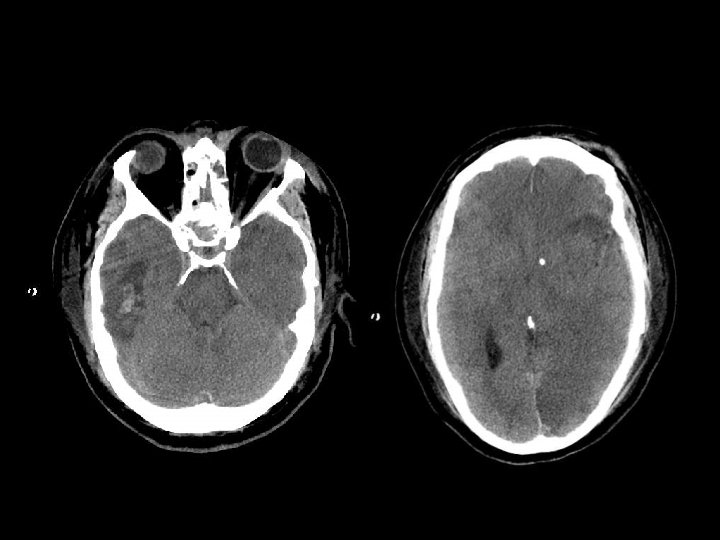

EPIDURAL HEMATOMA n Berlokasi antara skull dan periosteum n Akibat laserasi arteri meningea media atau vena dural n Dibatasi oleh sutura n Bentuk lentiform / bikonveks

PENANGANAN EDH n EDH > 30 cm 3 harus dievakuasi n EDH < 30 cm 3 dan ketebalan <15 mm dan pergeseran midline < 5 mm dan GCS >8 dapat diobservasi dengan serial CT